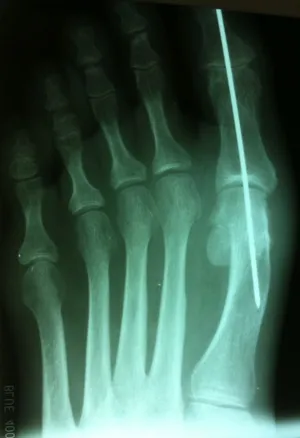

Varus position great toe after bunion surgery, the great toe is deviated laterally away from the lesser toes (left). Surgical procedure performed involved soft tissue correction and temporary fixation with a Kirschner wire (center). Several weeks after surgery the wire is removed and the great toe is now in rectus (straight) position.